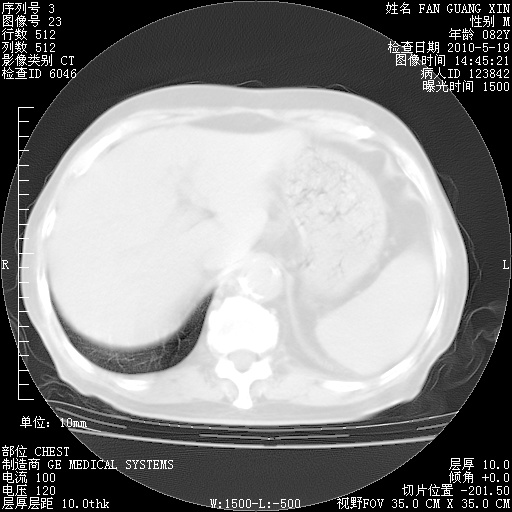

治疗3周后的肺部CT纵隔窗